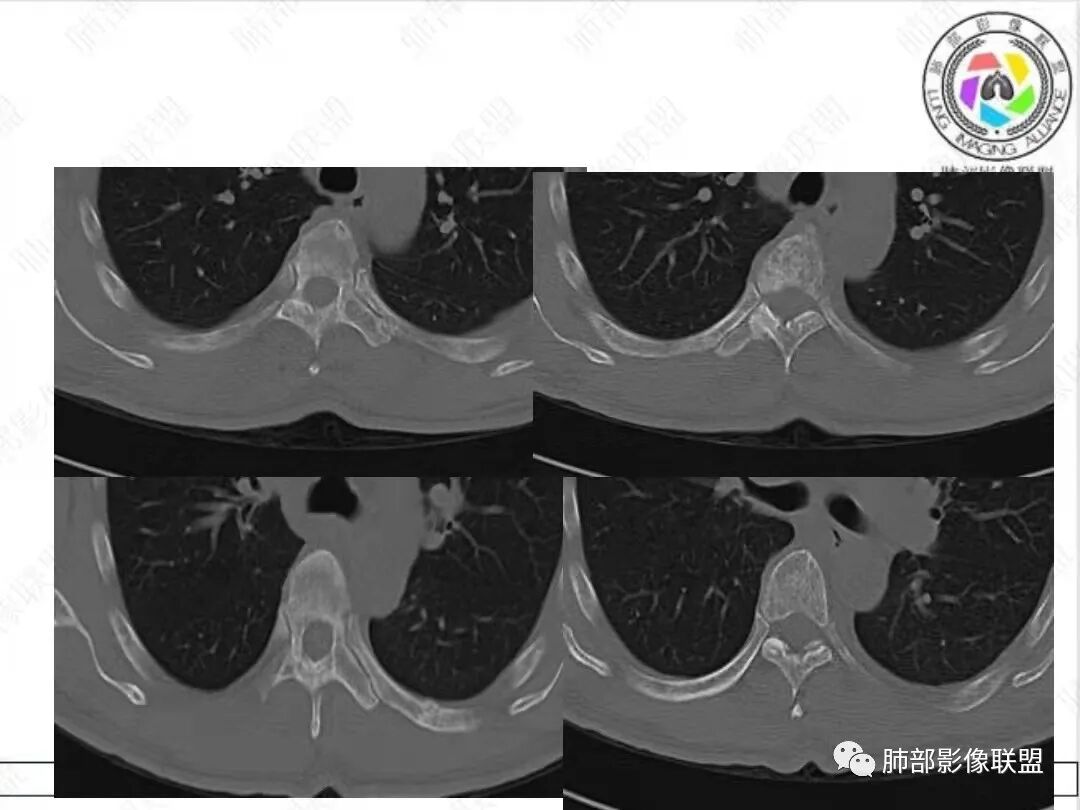

2、影像特点:胸部CT:平扫,前纵隔肿物,基本居中,与周围结构局部分界不清。增强后显示轻中度强化。肿块沿血管间隙侵袭性生长,左无名静脉受压明显变形受侵。纵隔、右肺门多处大小不等淋巴结,左侧内乳淋巴结稍增大。右侧瘤肺交界面光滑,左侧凹陷,肺组织未见明显受侵。右肺中下叶可疑小结节。胸椎及肋骨骨质增生性破坏。肋骨骨折。

很多老师提到前纵隔占位+血管肿块内漂浮+内乳淋巴结增大+轻中度强化=淋巴瘤,淋巴瘤确有上述特点,但本例血管漂浮不明确,病灶强化不均匀,胸椎及肋骨可疑增生性转移,应想到胸腺癌或不典型类癌的可能性。